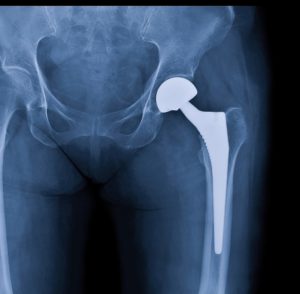

Xray scan of patient who have hip replacement and knee arthroplasty (knee replacement) treatment for Osteoarthritis knee, hip arthritis, Osteonecrosis of Hip. After surgery patient can walk normally

24 hours later, Margaret was wheeled into surgery. A radiology technician had taken an x-ray of her left hip. On the long bone of the thigh (femur), right below the ball that sits in the socket of the hip, was a fracture line. Margaret had broken her hip during the fall and needed a hip replacement as soon as possible.